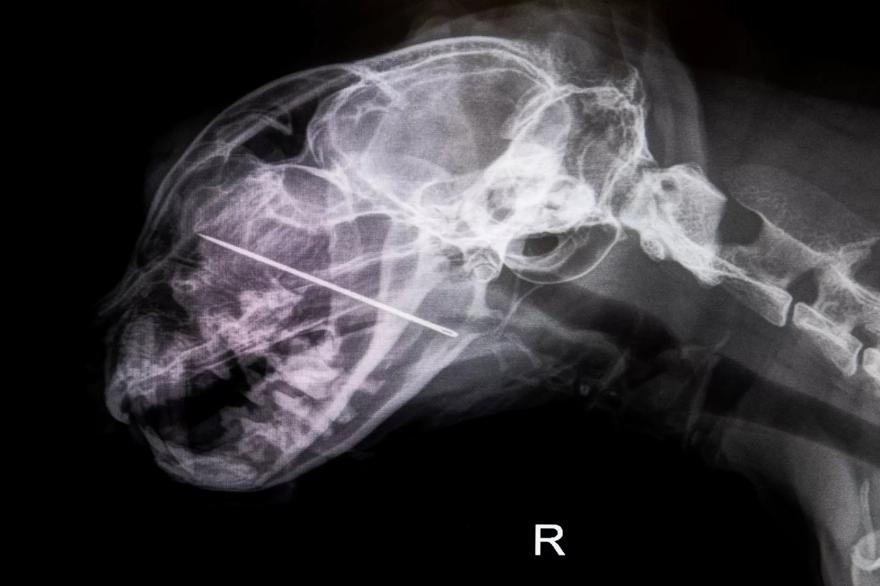

Αυτή την εβδομάδα, το DoveLewis Veterinary Emergency & Specialty Hospital στο Πόρτλαντ μοιράστηκε ότι ένας τοπικός γάτος με το όνομα Kevin, ο οποίος είναι “γνωστός για την περίεργη φύση του”, βρέθηκε στον κτηνίατρο αφού έβαλε τα πόδια του σε μια βελόνα ραψίματος, εν αγνοία των ιδιοκτητών του.

“Γρήγορα μετανιώνοντας για την απόφασή του, ο Κέβιν προσπάθησε να τα αναμασήσει, με αποτέλεσμα η βελόνα να καρφωθεί μέσα από τον σκληρό ουρανίσκο του και να επεκταθεί στη ρινική του κοιλότητα, με αποτέλεσμα να προκαλέσει τεράστια δυσφορία και κίνδυνο”, δήλωσε ο DoveLewis

Αν και η οικογένεια αρχικά δεν συνειδητοποίησε ότι τα προβλήματα του γάτου ήταν αποτέλεσμα της βελόνας, τον έφεραν σε επείγουσα περίθαλψη αφού ο Κέβιν άρχισε να κάνει εμετό και αντιμετώπιζε πρόβλημα κατάποσης. Από εκεί, παραπέμφθηκαν στο DoveLewis, όπου διαπιστώθηκε ότι “ο Κέβιν χρειαζόταν μια στοματική εξέταση με νάρκωση για να προσδιοριστεί η πηγή της δυσφορίας του και το σάλιο με γεύση αίματος που είδαν γύρω από το στόμα του”, σύμφωνα με την ανακοίνωση.

“Η ομάδα ανακάλυψε τη βελόνα ραψίματος ενσωματωμένη στο στόμα του Κέβιν, με το αμβλύ άκρο να πιέζει τη βάση της γλώσσας του”, συνεχίζει η ανακοίνωση πριν εξηγήσει ότι η βελόνα στη συνέχεια αφαιρέθηκε.